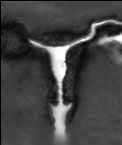

Ултразвуков преглед |

|

HSG Хистеросалпингографията (HSG) е рентегнова снимка използвана за установяване на запушвания на тръбите и маточни проблеми. Инжектира се контрастно вещество през шийката на матката и се прави рентгеновата снимка. Това изследване се прави обикновено след менструация и преди овулация.инжектирано контрастно вещество |